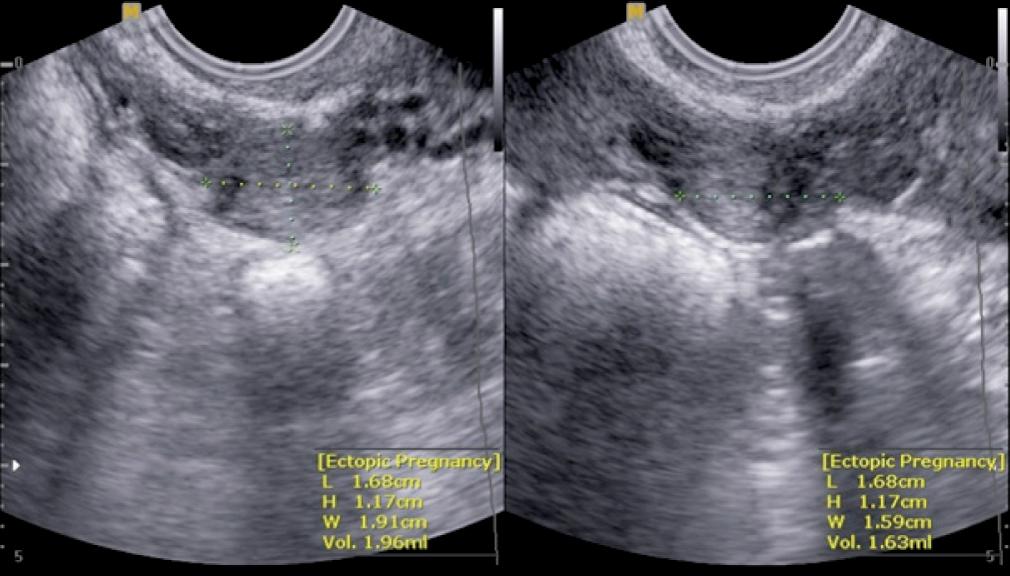

Fig. 1.

TVS of an ectopic mass consistent with EP of 19 mm. In terms of its size, the mass meets the eligibility criteria for MTX therapy